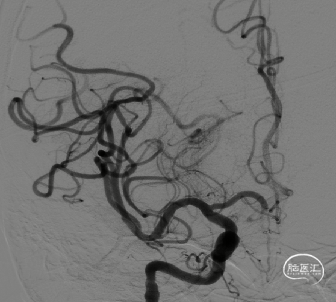

8F导引导管在多功能管及泥鳅导丝导引下直接进入右侧颈总动脉,此时Skathi远端通路导管尾端连接自制50ml负压注射器一路裸奔抽吸至C5段,反复抽吸3次,抽出大量血栓,回血通畅后,轻轻冒烟提示颈内动脉通畅,大脑中动脉M1远端闭塞,与取栓前后循环造影显示情况一致。

大脑中动脉M1段血栓采用SWIM技术-抽拉结合,避免血栓逃逸。

一次SWIM取栓,成功血管再通,达到mTICI分级:3级。